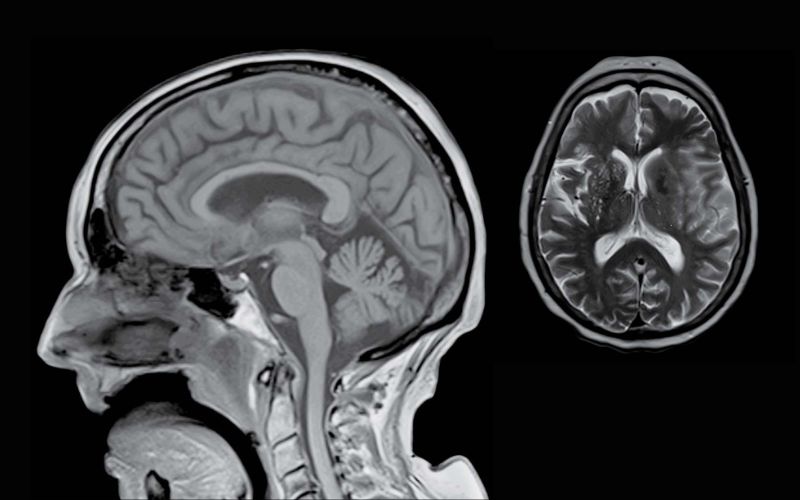

3T MRI is recommended over 1.5T for better visualization of neurological tissue, the spinal cord, protein build up in the brain, tumor detection, MS lesions, structural abnormalities, and vascular blood flow. Structures are more easily identifiable with 3T MRI because of the higher quality signal to noise ratio.

Benefits of 3T MRI are the ability to obtain images demonstrating miniscule slices as low as 1mm slice thickness, which aids in diagnosing difficult and complex cases. Structural detail is greatly enhanced with a 64-channel neurovascular coil for head and neck imaging.